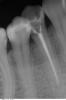

SergioS Опубликовано 14 февраля, 2013 Поделиться Опубликовано 14 февраля, 2013 Прошу помощи разобраться:Пациентка была у терапевта:30.01.- орто,44 под витапекс, временная пломба. перкуссия 44 болезненна2.02. - осмотр болит меньше.9.02 - боли усилились перкуссия 45 резко болезненна, 45 под Vitapex. Амоксиклав.12.02. - мой прием: Из анамнеза 3 дня назад перенесенная ветрянкатемпературы нет, ассиметрия лица(отек щечной области справа), гиперемии кожн покровов нет. Слизистая в области 46-43 со щечной сторны гиперемирована.отечна, флуктуации нет. 46 - подвижность 0-I степени. Перкуссия 46,45.44,43 резко болезненна. Что предпологаете? Мне еще корни 46 не нравятся(короткие они(я понимаю.что Попова-Годона). Ссылка на комментарий

SergioS Опубликовано 14 февраля, 2013 Автор Поделиться Опубликовано 14 февраля, 2013 я бы проверил зубы на витальность ну и методом исключения итдЭОД нет. Перед этим терапевт проверял их на витальность методом разогретой гладилки. Отмечал реакцию 46,43 в пределах нормы, а вот на 44,45- короткую реакцию( без следового компонента). Ссылка на комментарий

DoctorN Опубликовано 14 февраля, 2013 Поделиться Опубликовано 14 февраля, 2013 Терапевт тот же сейчас тока пошел открывать эти оба два зуба.витапекс,если мне не изменяет память-это плотная масса с гидроокисью кальция.в некоторых случаях авторы инструкции предлагают обтурировать им канал на постоянку.по первоначальному снимку дохлый,причем прилично,44,и скорее всего уже начались явления эксудации в периапикальном пространстве.канал обтурируется витапексом-отток нет(а если еще туда терапевт протолкнул файлом кусочек сдохшего нерва-между нами-)вот и результат.на мой взгляд с 6м и 7м все в порядке Ссылка на комментарий